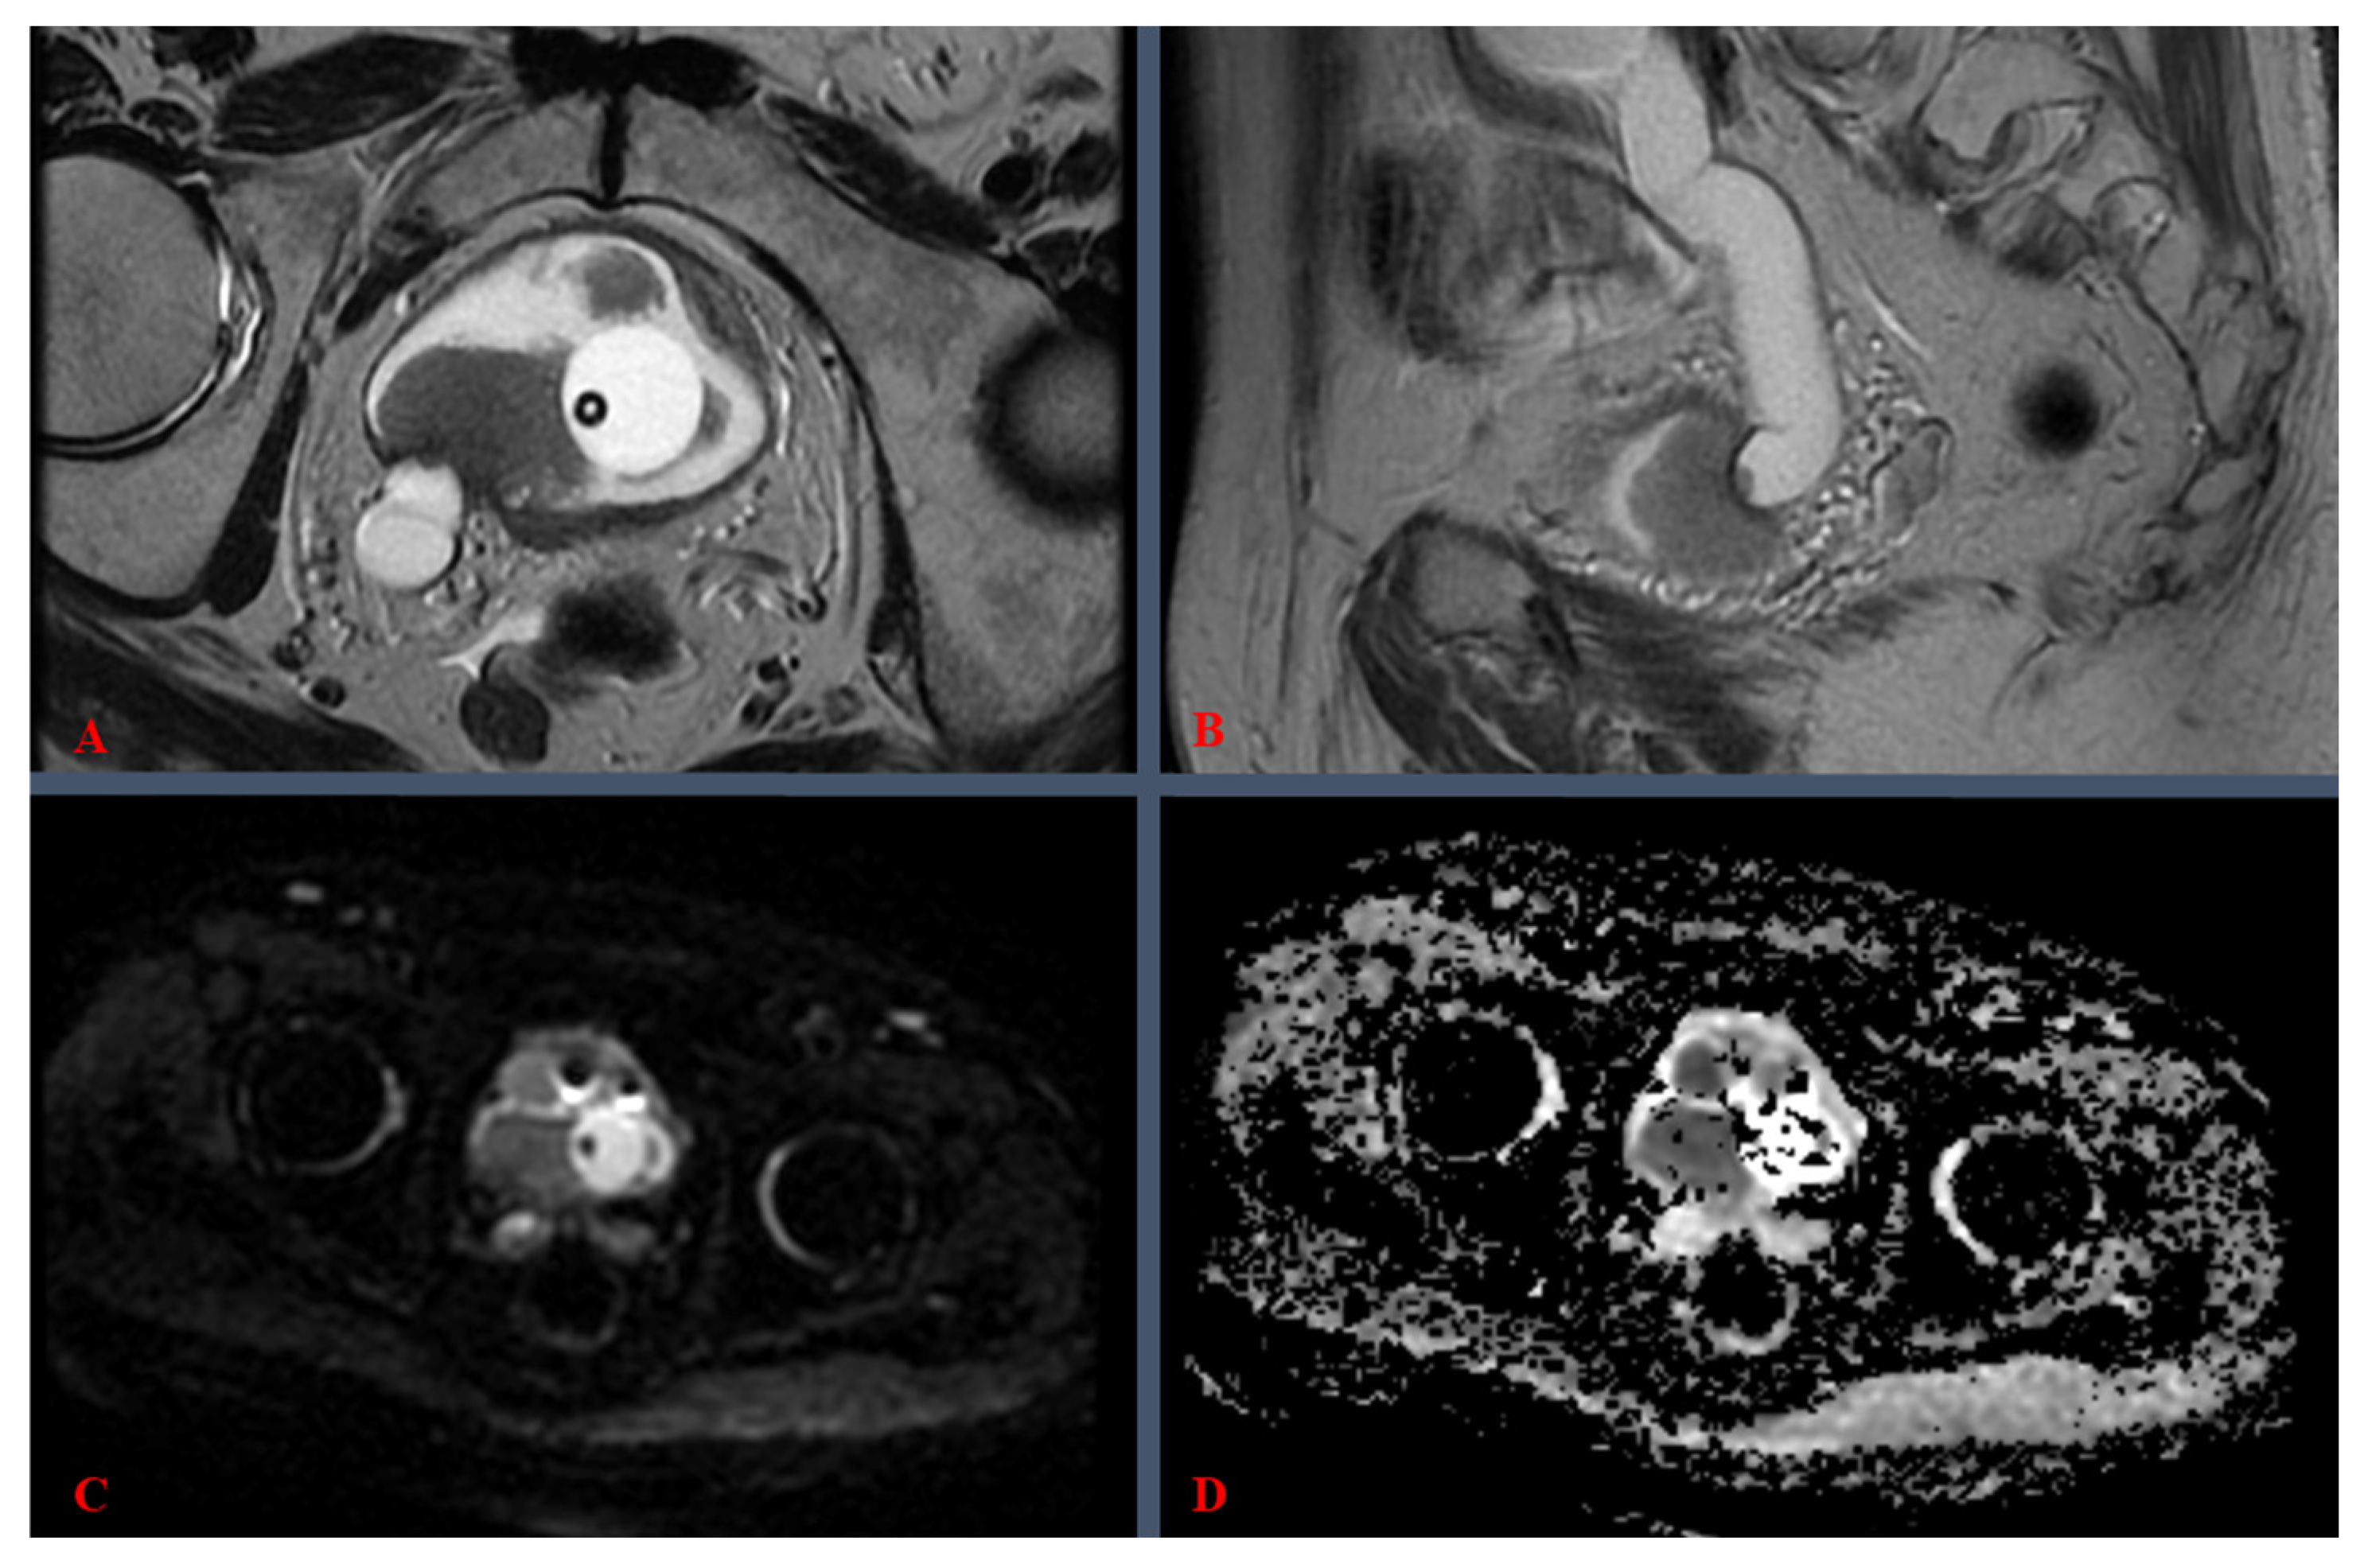

3.1. Definitions, Procedural Details, and Clinical Considerations

3.3. Imaging Parameters, Protocols, and Technical Specifications